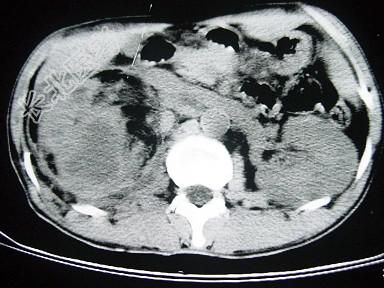

- 单项选择题女,43岁, 右腰部疼痛不适2年余,加重3天, CT及MRI检查如图,应诊断为 ( )

A、右肾癌

B、右肾错构瘤合并出血

C、右肾脂肪瘤

D、右肾脂肪肉瘤

E、右肾海绵状血管瘤